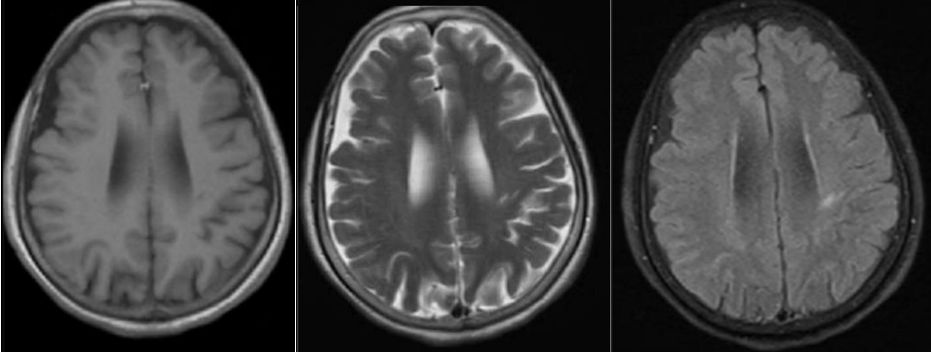

37岁男性,言语不清伴四肢震颤3个月入院。

答案:神经梅毒。患者青年男性,双侧海马萎缩明显,梅毒呼之欲出。要注意和慢性酒精中毒鉴别。